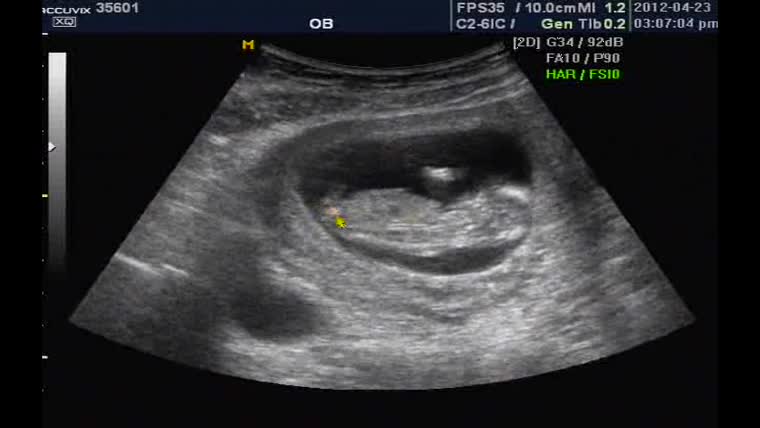

출산 날짜: 2012년 11월 09일

출산 시간: 오전 11시 56분

아기 체중: 4.16kg

아기 성별: 남

그도 그럴것이 어렵사리 분만한 아기 덩이의 몸무게가.. 후후... 4kg가 넘었었죠!!!

정확히 4.16kg이었었죠. 후훗;;